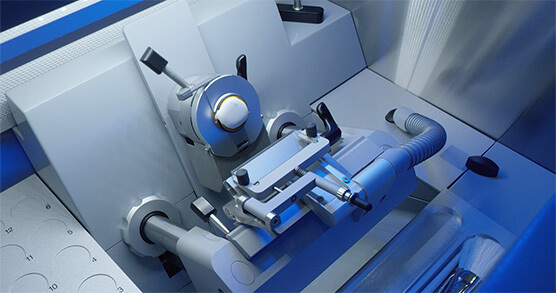

相关实验室

相关实验室